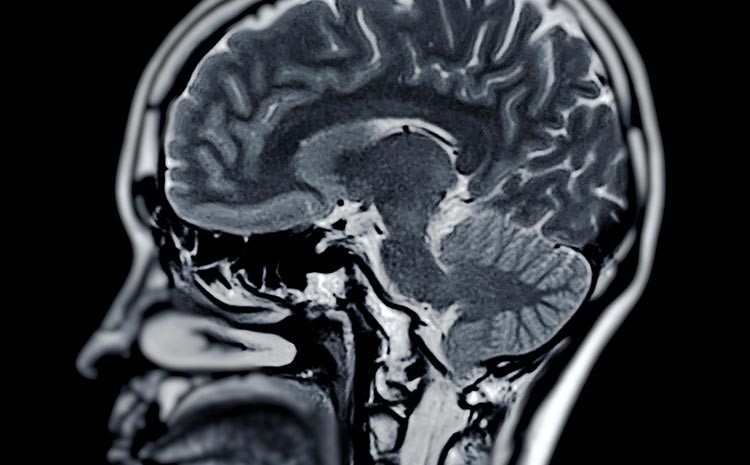

Muitos diagnósticos acontecem de maneira inesperada. Uma pessoa pode realizar uma tomografia ou ressonância por conta de uma dor de cabeça persistente, um trauma ou outro problema de saúde, e o aneurisma aparece como um achado incidental. Esse tipo de descoberta é cada vez mais comum com o avanço da tecnologia de imagem.